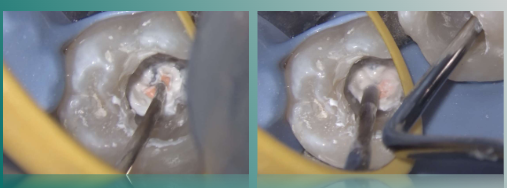

根管内注入生物陶瓷SP糊剂

近远中根管内放入牙胶尖

携热器切断至距很尖4-5mm处

垂直加压根管内牙胶

热牙胶回填近中根管,垂直加压。

远中根管回填热牙胶,垂直加压,将牙胶压入狭区。

远中根管继续回填热牙胶,垂直加压C形区域,将牙胶压入狭区。

远中根管继续回填热牙胶,少量多次回填,耐心仔细加压。

超声清洁髓腔

根充后髓腔内状态

37%磷酸选择性酸蚀,冲洗,吹干,涂布八代粘接剂,光照20s。

流体树脂封闭根管口,膏体树脂分层充填窝洞。

完成冠方封闭